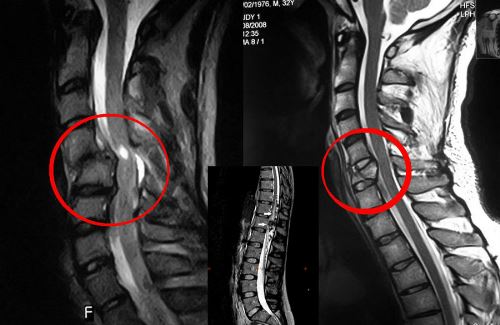

а — рентгенограмма поясничного участка позвоночника, показывающая эрозию левой ножки L3 б — скан МРТ, показывающий острую компрессию спинного мозга. Большая постериорная масса, покрывающая свыше 3 позвонков, сжимает спинной мозг.

Исследование должно включить обзорную рентгенограмму позвоночника

, которая может показать наличие множественных костных метастазов, параспинальную массу, раздавленный перелом в области боли, или менее очевидные изменения, такие как эрозия ножки. Обычный рентген делают не часто. Наиболее полезна в исследовании МРТ, она показывает пораженные места с высокой точностью и обычно дает ясный вид степени разрушения (объема опухоли внутри и снаружи от спинного мозга) и присутствия множественных повреждений. При недоступности МРТ надежной альтернативой служит КТ в комбинации с миелографией.